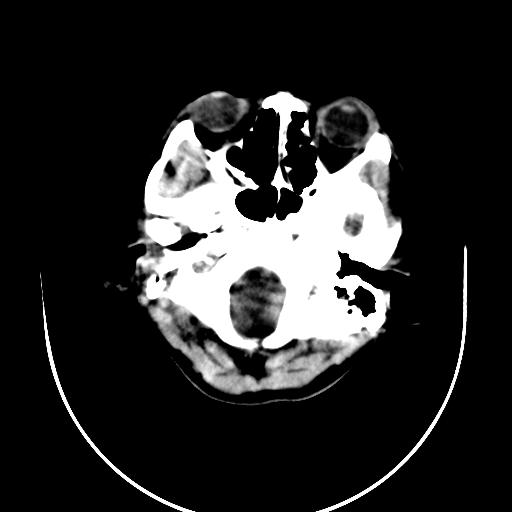

标题: CT10010:女/24岁,癫痫一周,发作时间不固定. [打印本页]

标题: CT10010:女/24岁,癫痫一周,发作时间不固定.

右侧额叶正常吗?

右额叶镰旁饱满.

右侧外侧沟?中央沟?可能有问题,不知以前有没有癫痫过,最好是增强下,排除局部血管畸形等病变

倒数第6幅图中线结构有点偏,而侧脑室额角未见异常,可结合增强扫描。